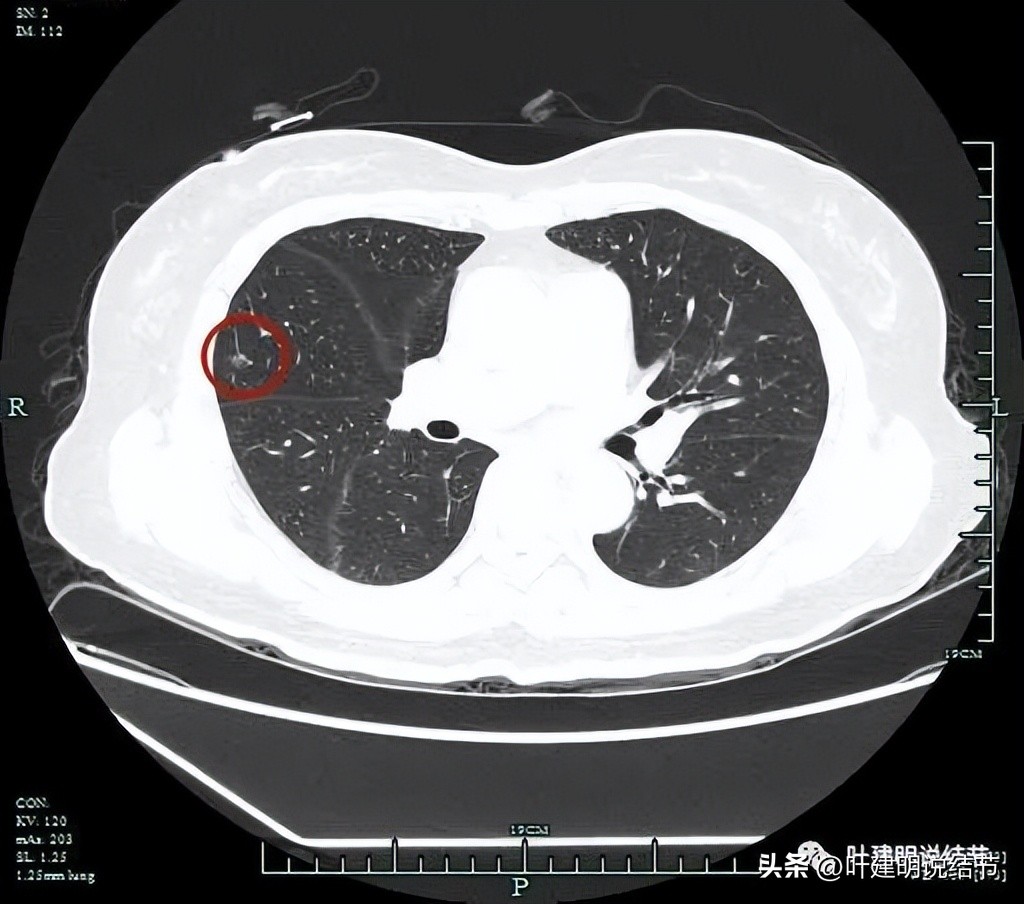

密度整体不均匀。

微小血管进入明显且多处;粉色箭头示病灶内部偏实性成分也明显。

血管征以及磨玻璃成分,病灶轮廓与瘤肺边界清。我们见进入的这支血管是有异常增粗的,它不是越往远心端越细,而且基本同样粗细走向病灶,到了病灶内部后显得散开来,密度反而更显高点。